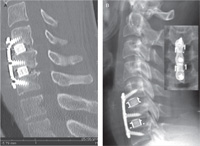

Fig. 5 F/E X-rays demonstrating a

mechanically stable one-level graft with

plate fixation.

In the Plated Group, 100% fusion rate was achieved by 6

months postoperatively and remained unchanged throughout

patient follow-up. Grafts demonstrated no movement on flexion/extension X-rays (Fig. 5). There were no incidences of

radiological complications such as graft subsidence,movement

or fracture. One X-ray demonstrated a 2 mm loss of disc space

height; however, this did not qualify as graft subsidence and

there were no associated symptoms developing over the course

of 26 months of follow up.